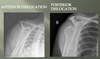

What type of shoulder dislocation is more common and why?

Anterior, more than 90%

Anterior muscular and ligamentous support is much less robust than the posterior aspect

What are the associated causes of posterior shoulder dislocations?

A

Seizures

Electric shock

High-energy dislocation e.g. car crash

What do these X-rays show?